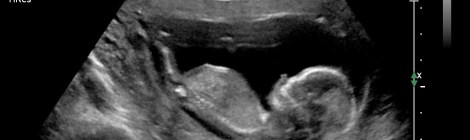

• Zwangerschap

• Fit tijdens je zwangerschap

• Geboorteplan

• Moeders voor moeders

• Zwangerschapsmassage